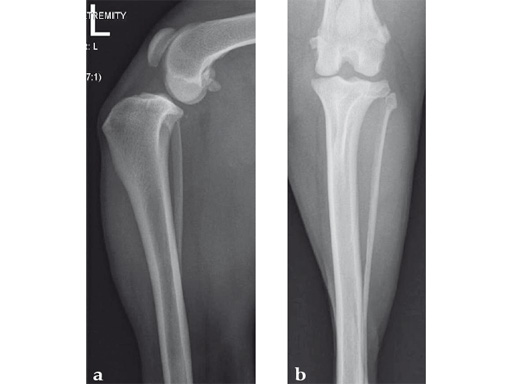

Case 2: Cat

A 10-year-old female, spayed, 6.0 kg cat had a partial tear of the left cranial cruciate ligament, meniscal mineralization, and a medial meniscal tear. The cat was treated with a partial meniscectomy and TPLO . A 2.0 mm TPLO plate was perfect for this cat due to the slope of the tibial plateau (25) and the size of the cat. Three 2.0 mm locking screws were used proximally and three 2.0 mm cortex screws were used distally. The contour of this plate does not perfectly match the contour of the proximal tibia, but use of locking screws in this segment avoids any potential angulation of the segments as the screws are tightened. The cat healed uneventfully and returned to normal function.